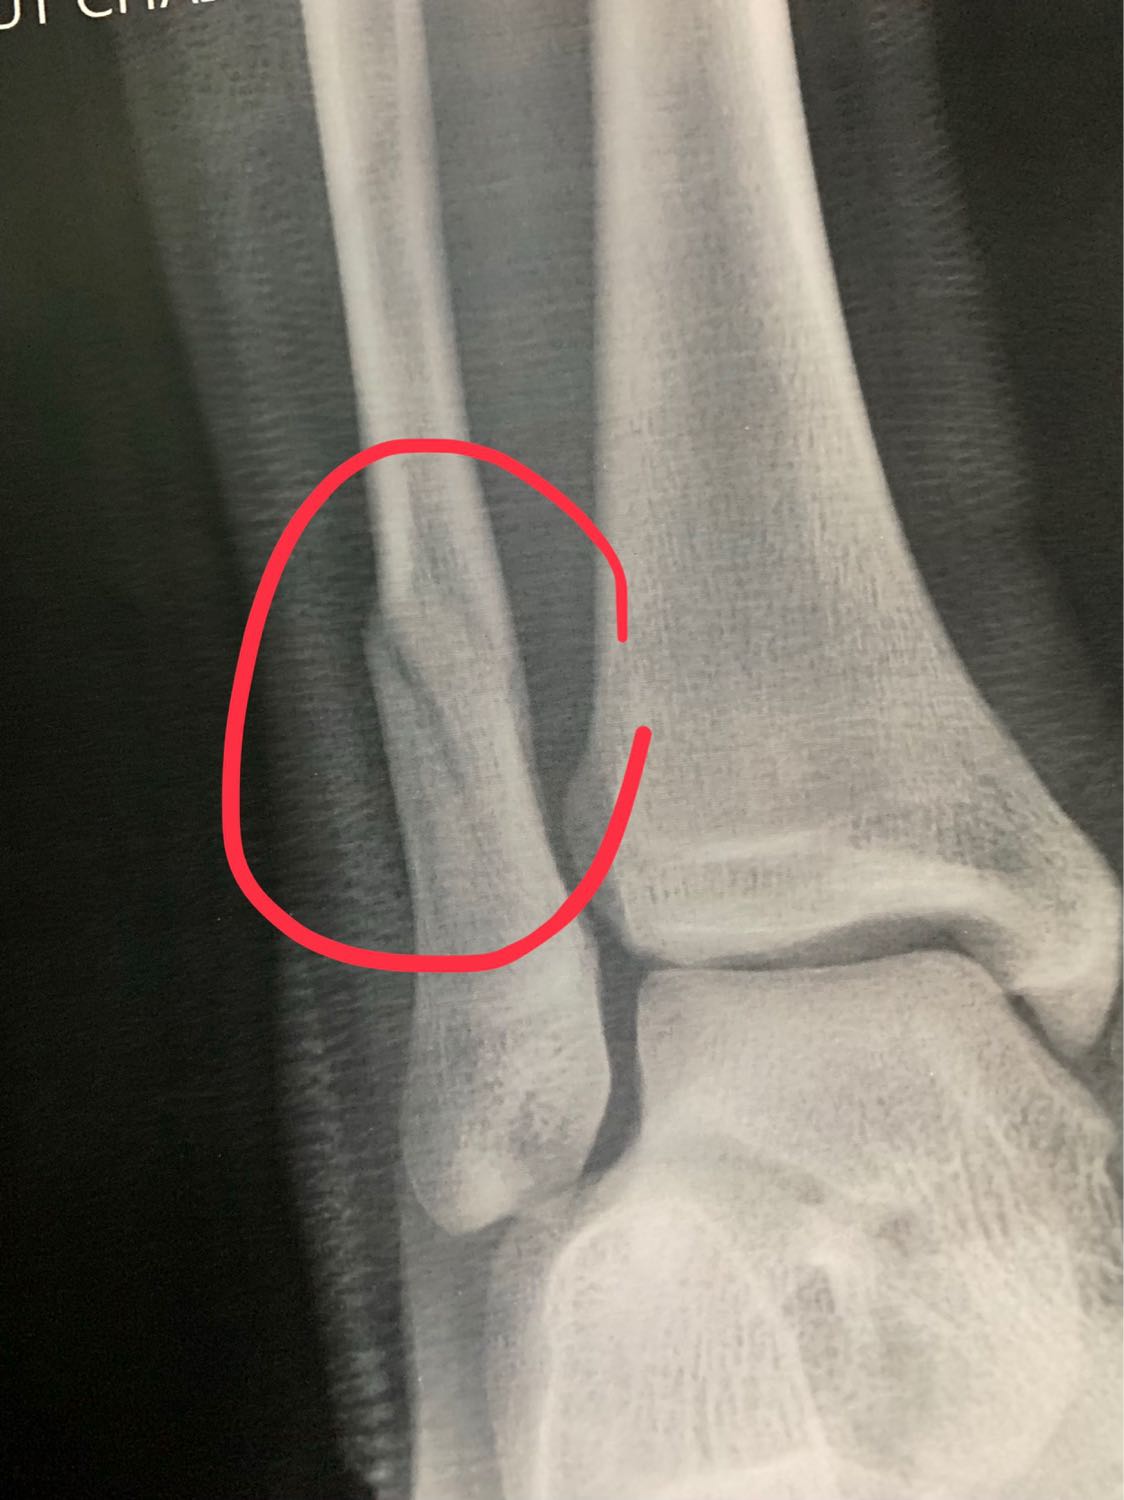

น้องอายุ16 กระดูกร้าว ควรต้องผ่าตัดไหมครับ

ตามภาพข้างบนเลยครับ คือไปหาหมอมาหลายหมอ มีทั้งแนะนำให้ผ่า และไม่ต้องผ่า แต่ส่วนตัวคือไม่อยากให้น้องผ่า เพราะคิดว่าน้องชายอายุยังน้อย กระดูกน่าจะเชื่อมต่อกันเร็ว เลยไม่อยากให้ผ่า เลยอยากรบกวนสอบถามผู้มีความรู้ หรือประสบการณ์หน่อยครับ จะได้ตัดสินใจว่าจะทำไงต่อไป พ่อแม่ก็2จิต2ใจครับ

ปล. กระดูกตรงน่องครับ